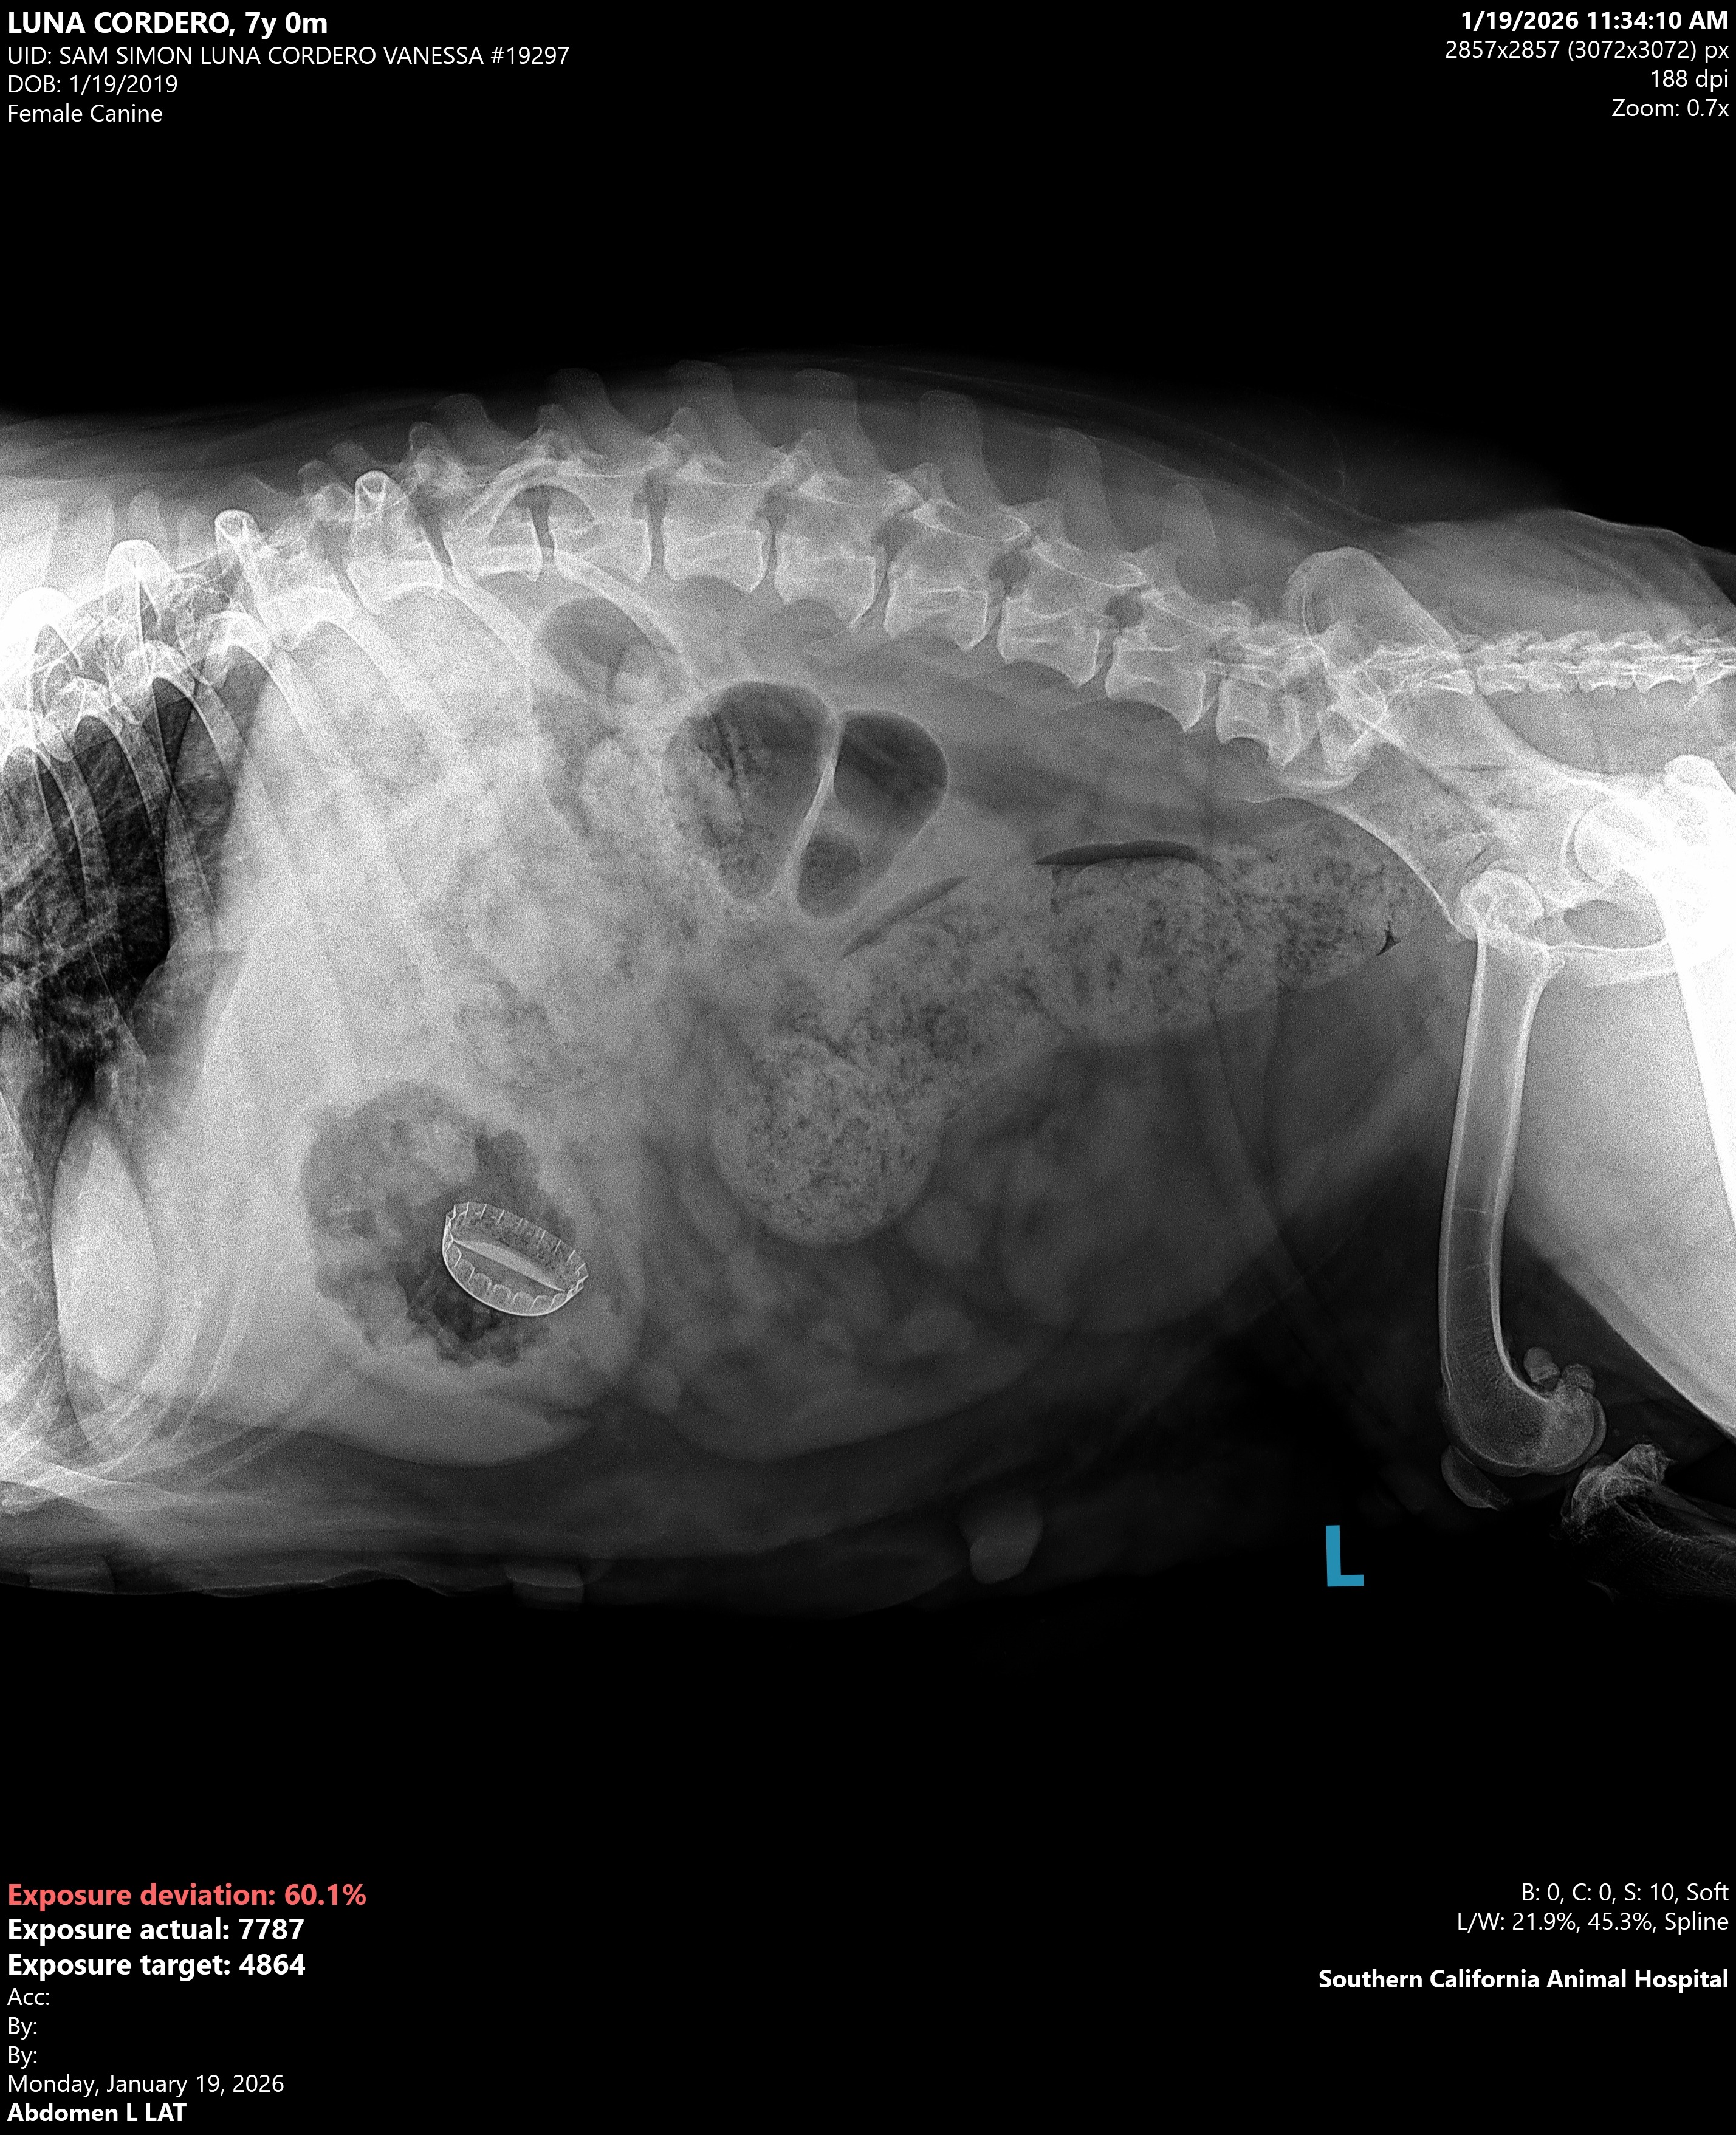

UPDATE: she has been to the vet and after the x-rays we have found a metal bottle cap in her stomach. We don't know how long it's been there. So her surgery is even extra urgent after this new information. She also has arthritis in her spine and her teeth are broken and her dew claws have been removed. This poor girl has really been abused. Please help us spread the word to get her the surgery she needs.